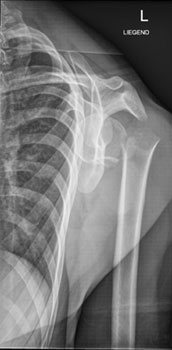

Die Röntgenaufnahme der Schulter in zwei Ebenen ist die Untersuchung der Wahl zur Beurteilung der Knochenstrukturen und der Gelenkstellung.

Hier sehen Sie die Aufnahmen im vorliegenden Fall: